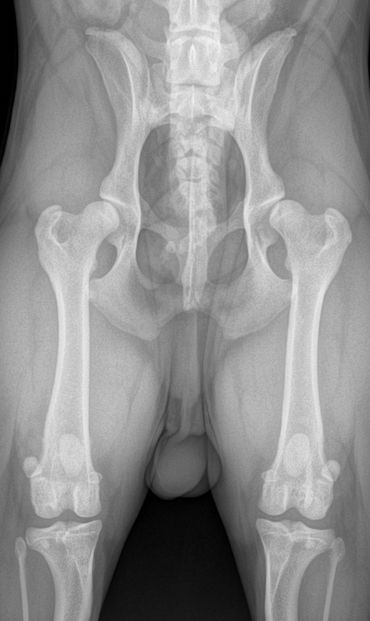

This technique requires 3 xrays views be taken while the dog is sedated.

The three views are

Often the distraction view shows greater laxity (looseness) in the hip than the hip extended view. This is because the hip extended view often masks hip laxity due to the position the socket is stretched into. This is why both views are required to be assessed with PennHIP scoring. The compression view allows the radiologist to assess the fit of the femoral head (ball) into the acetabulum (socket).